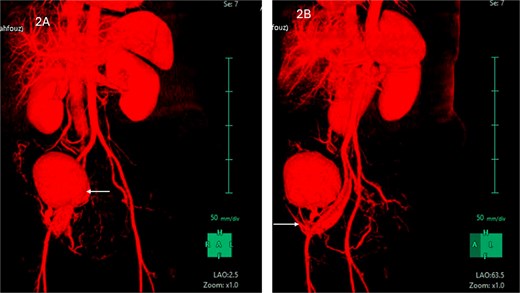

CT scan revealed evidence of large right iliac fossa soft tissue mass, measuring 8.5 × 8.2 × 8.4 cm, displacing the adjacent abdominal and pelvic organs with significant peri-lesional fat strandings. The mass shows homogenous hyper enhancement in post contrast with peripheral slight enhancing area [3.3 × 1.8 cm] with adjacent bowel loops tethering with peritoneal thickening. There were multiple adjacent para-aortic, right external iliac, and common iliac lymph nodes enlargement (Fig. 1). The mass vessels were arising from the right external iliac artery and vein (Fig. 2).

(A) CT abdomen with contrast demonstrating the mass in the right iliac fossa. (B) The image is rotated to show the blood supply from right external iliac artery and vein.